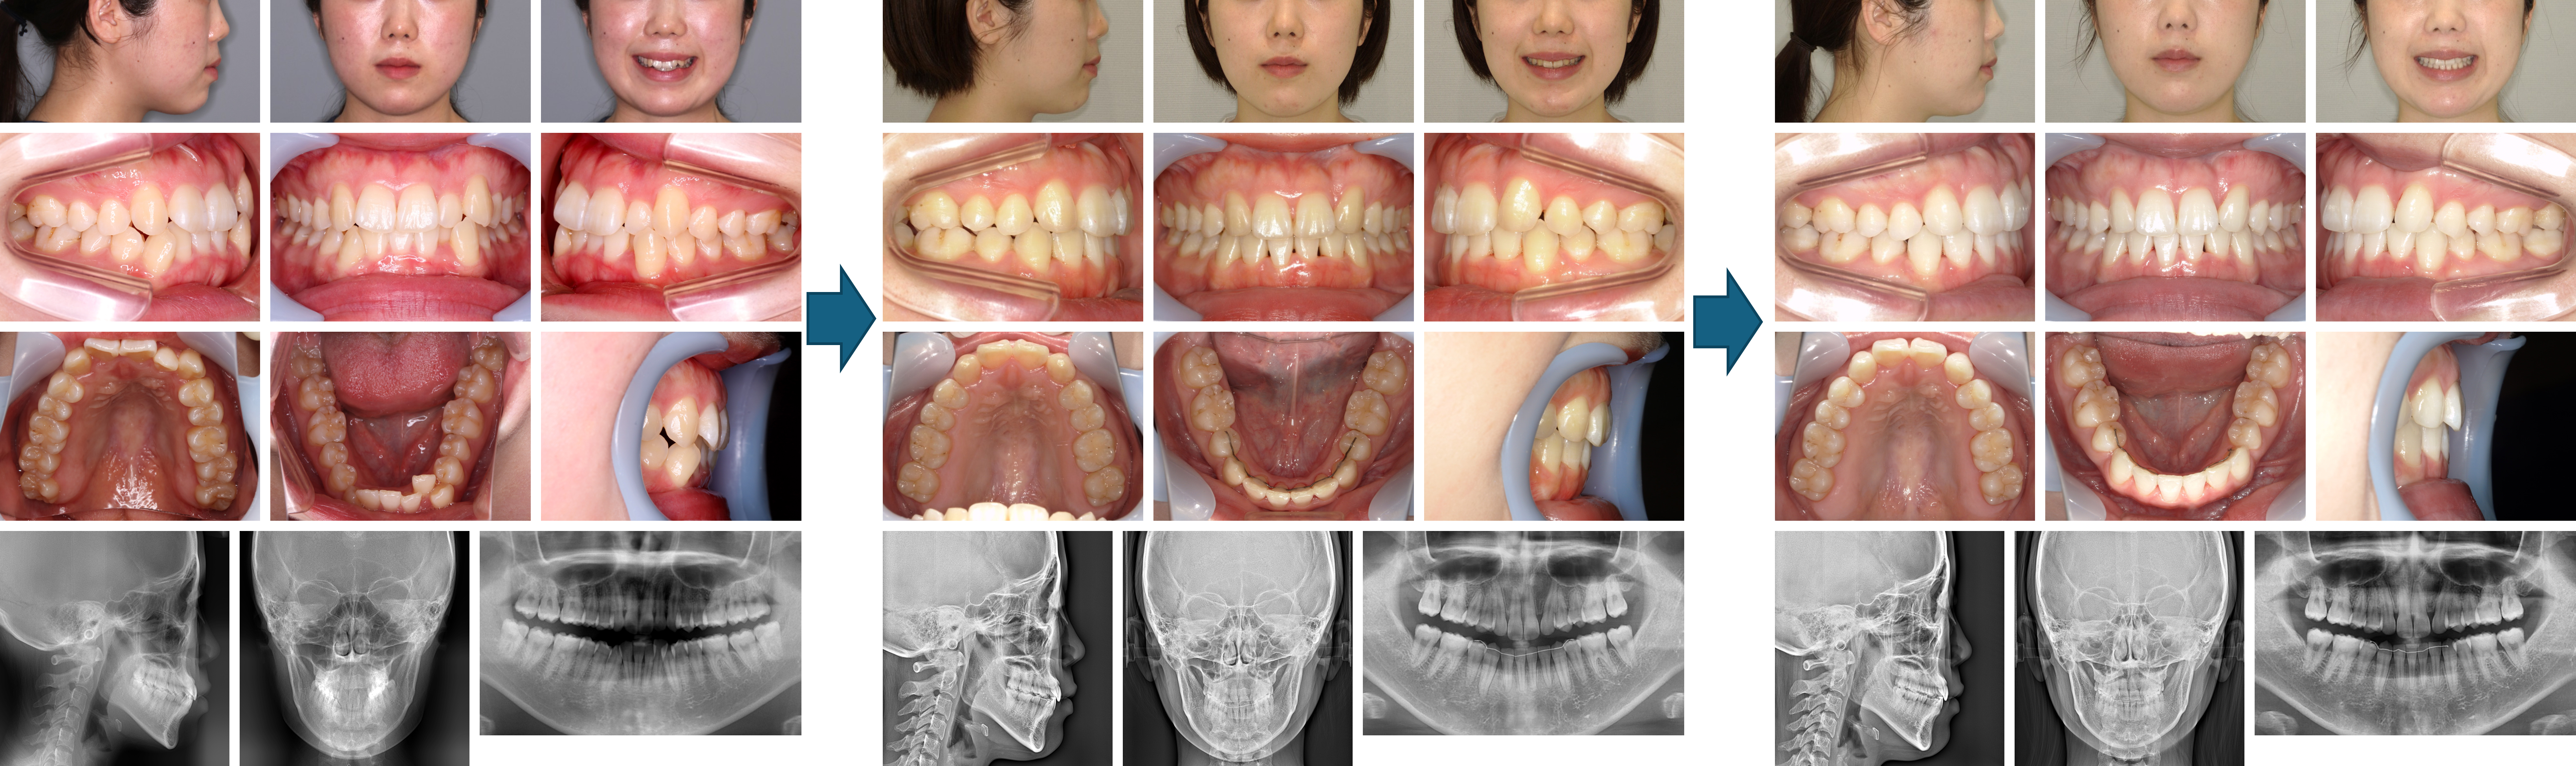

【治療例】初診時年齢:24歳2か月 / 性別:女性 / 主訴:上の歯2本が内側にはえていることと右上の八重歯が気になる

症例の概要:上下とも歯が大きくさらに下顎歯列に対して上顎歯列が狭かったため、上顎はクワドヘリックス装置で歯列の拡大を行った後、上下とも歯を抜歯する治療法を選択した。下顎骨の後退位と右方偏位が認められたが、トランスパラタルアーチとハイプルヘッドギアをしてくれたおかげで、治療後は顔貌の改善と緊密な咬合を獲得することができた。

主訴:口元の突出感と上の歯2本が内側にはえていることと右上の八重歯が気になる

診断名:下顎骨が後退位と右方偏位した骨格性Ⅱ級、ハイアングルの上顎前突症例

使用した主な装置:マルチブラケット装置、クワドヘリックス、ハイプルヘッドギア、トランスパラタルアーチ、顎間ゴム

抜歯/非抜歯および抜歯部位:抜歯(上下顎両側第一小臼歯)

治療期間:2年4か月

治療回数:25回

リスクの副作用:歯の移動や抜歯による違和感や疼痛、口内炎、歯肉退縮、歯根吸収が生じることがある